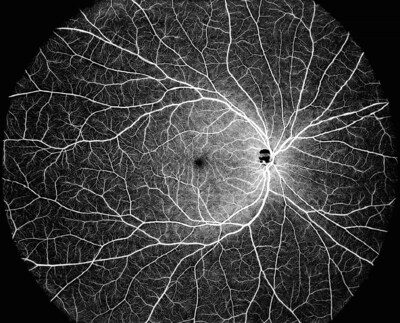

使用 DREAM OCT 進行單次 130 度 OCTA 影像拍攝

DREAM OCT 能覆蓋超寬領域的單次掃描,提供 130° 的光學相干斷層掃描血管成像 (OCTA) 影像。DREAM OCT™ 的 12 mm 超深度掃描可對脈網膜、視網膜以及大部分玻璃體空間進行優異的成像。超深度前段掃描能力達到 16.2 mm(空氣中),只需一次掃描,即可完成從角膜到玻璃體前部的完整前段掃描。較長的波長,可穿透晶狀體 (Lens) 或玻璃體 (Vitreous) 的不透明層。